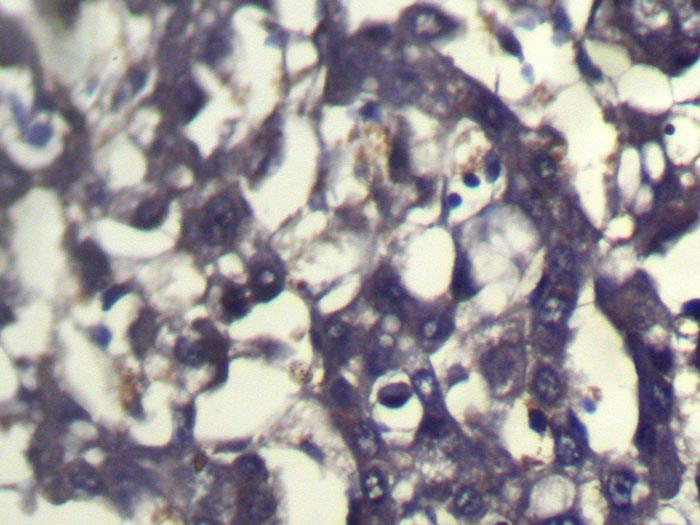

Immunohistochemical analysis of paraffin-embedded Human Liver cancer tissue using #40229 at dilution 1/100.